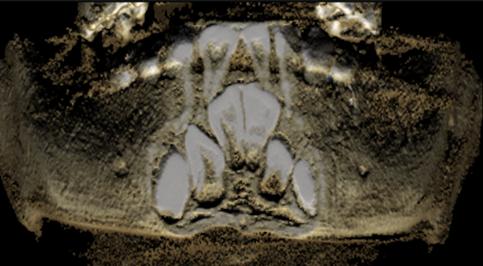

Frecuencia del segundo conducto en raíz mesiovestibular del primer molar maxilar con haz de cono.

Frequency of the second canal in mesiovestibular root of the maxillary first molar with cone beam.

Yuri Carlos Sánchez, Abner Jamil Gutiérrez